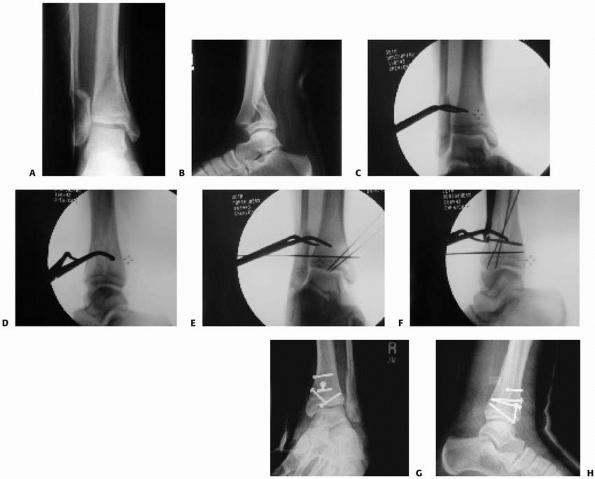

![]() |

FIGURE 26-16 Triplane with deltoid injury and syndesmosis widening with stress views. A,B. Injury films. C-E. Postoperative films.

|

FIGURE 26-17 A,B. Deltoid and possible syndesmosis injury associated with triplane fracture pattern.